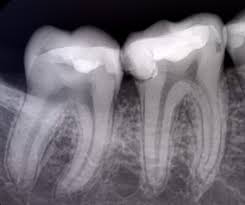

Si une femme est enceinte ou croit pouvoir l'être, elle doit le signaler. Visualiser ce qui ne peut pas etre vue a l'oeil nue lesion apex ou kyse voir le developement et croissant voir l'evolution du traitement confirme.

Elle permet de détecter les problèmes et ainsi l'élaboration d'un plan de traitement puis celle d'un devis précis devient possible. Une radiographie dentaire se réalise d'une façon simple, rapide et sans douleur. La radiologie est un complément d'examen indispensable pour un bon diagnostic.

Mise au point de l'odq. La radiographie est indispensable pour l'étude de l'état des mâchoires et des dents. Prise du cliché de radiographie dentaire.

Pour que la radio soit réussie il. La radiographie est indispensable pour l'étude de l'état des mâchoires et des dents. Le patient doit signaler si une radiographie semblable a été récemment réalisée.

Le patient doit signaler si une radiographie semblable a été récemment réalisée. Les radiographies dentaires permettent de déceler les problèmes invisibles à l'examen visuel et donc, d'éviter qu'ils ne s'aggravent. C'est une radiographie de petite taille, prise dans la bouche du patient.